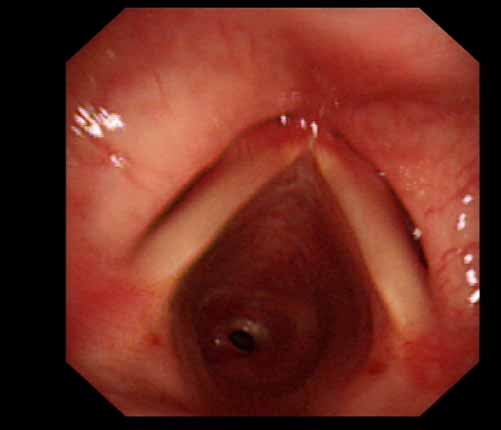

患者李某某,女,45歲,因氣管插管咳嗽、喘憋10天入院。頸部CT檢查示聲門下約20mm處氣管明顯狹窄,狹窄段長約26mm,最窄處直徑約4.4mm。支氣管鏡檢查見聲門下約2cm氣管呈漏斗狀縮窄,直徑約4-5mm,支氣管鏡無法通過。經(jīng)科室討論,決定行電子支氣管鏡下氣管球囊擴張治療。與患者及家屬充分溝通并經(jīng)三方見證談話簽署知情同意書后,在患者持續(xù)吸氧、局麻下,科主任于世倫主任醫(yī)師帶領(lǐng)治療小組為患者實行電子支氣管鏡下氣管球囊擴張術(shù)。手術(shù)過程順利,出血量很少,術(shù)后患者呼吸困難癥狀即可明顯緩解。10天后行二次擴張,患者日?;顒訜o明顯喘憋,二次術(shù)后5天出院。

術(shù)前聲門下的漏斗樣狹窄口